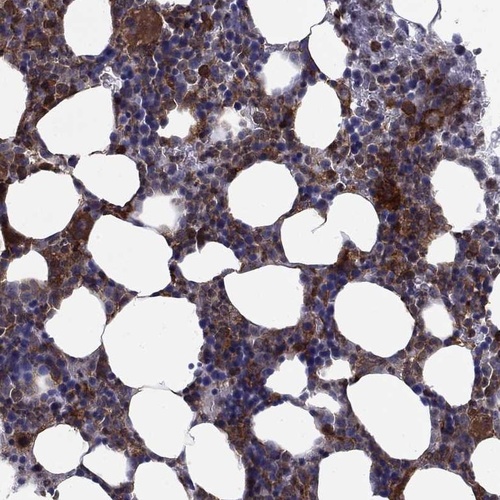

Immunohistochemistry analysis in human bone marrow and skeletal muscle tissues using Anti-PLCB2 antibody. Corresponding PLCB2 RNA-seq data are presented for the same tissues.